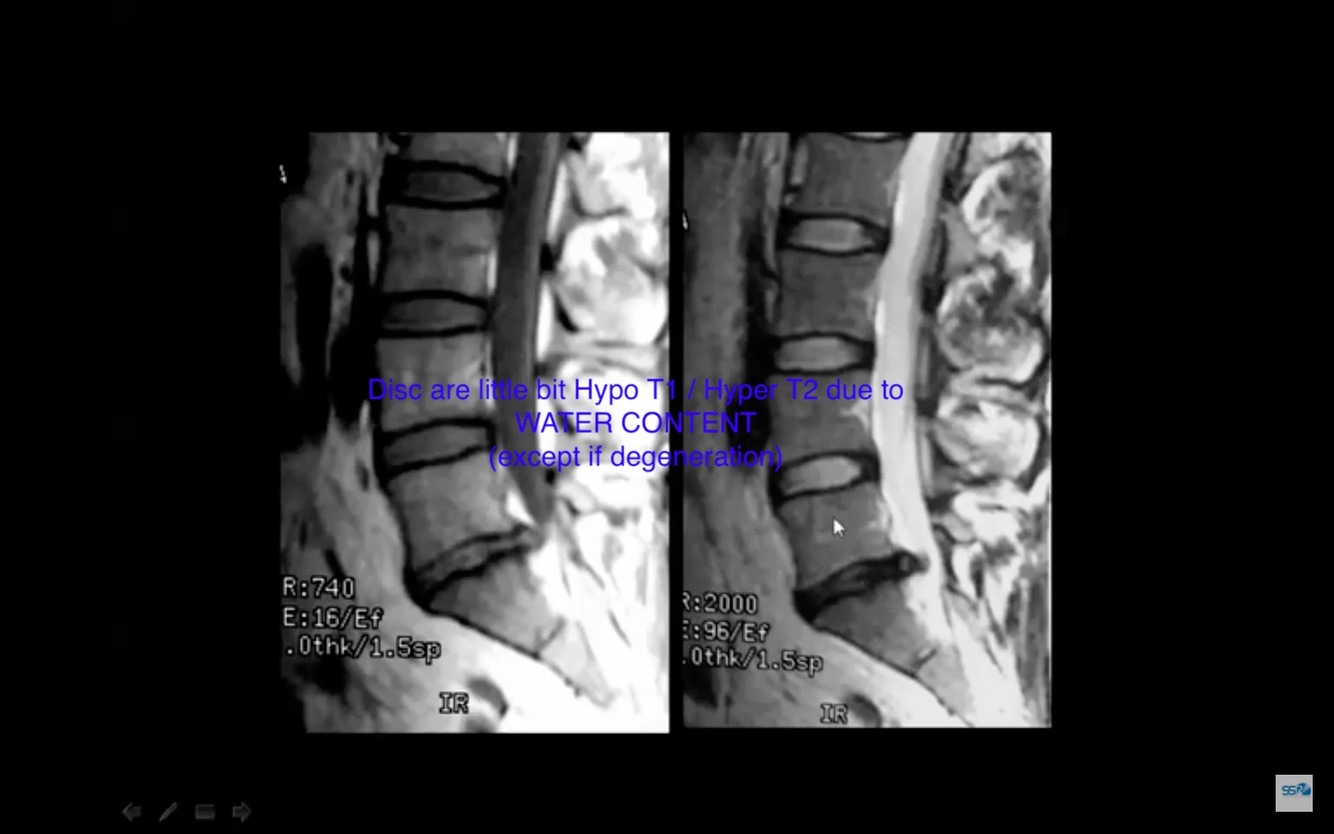

How`s the signal difference between discs and bone marrow?

Disc: Iso T1 / Iso T2

Bone Marrow has fat: High T1 / Low T2